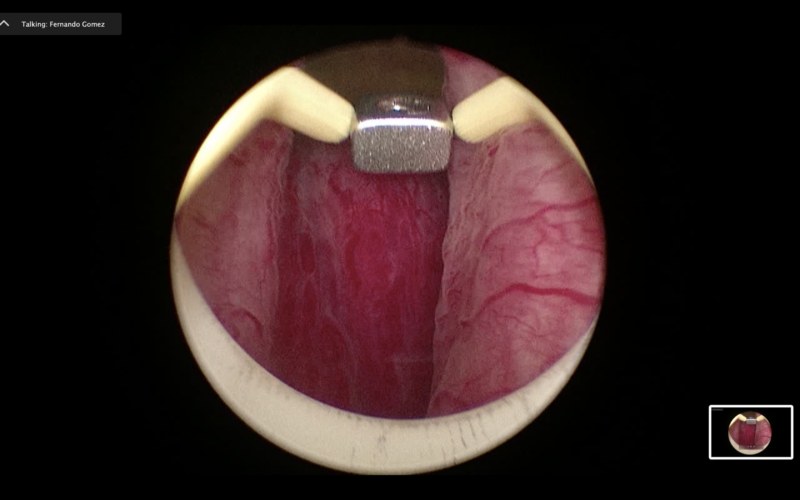

- το προστατικό αδένωμα αποκολλάται από την κάψα με τη βοήθεια του ειδικού ηλεκτροδίου εκπυρήνισης (εικόνες 1-4)

Εικόνες 1-4